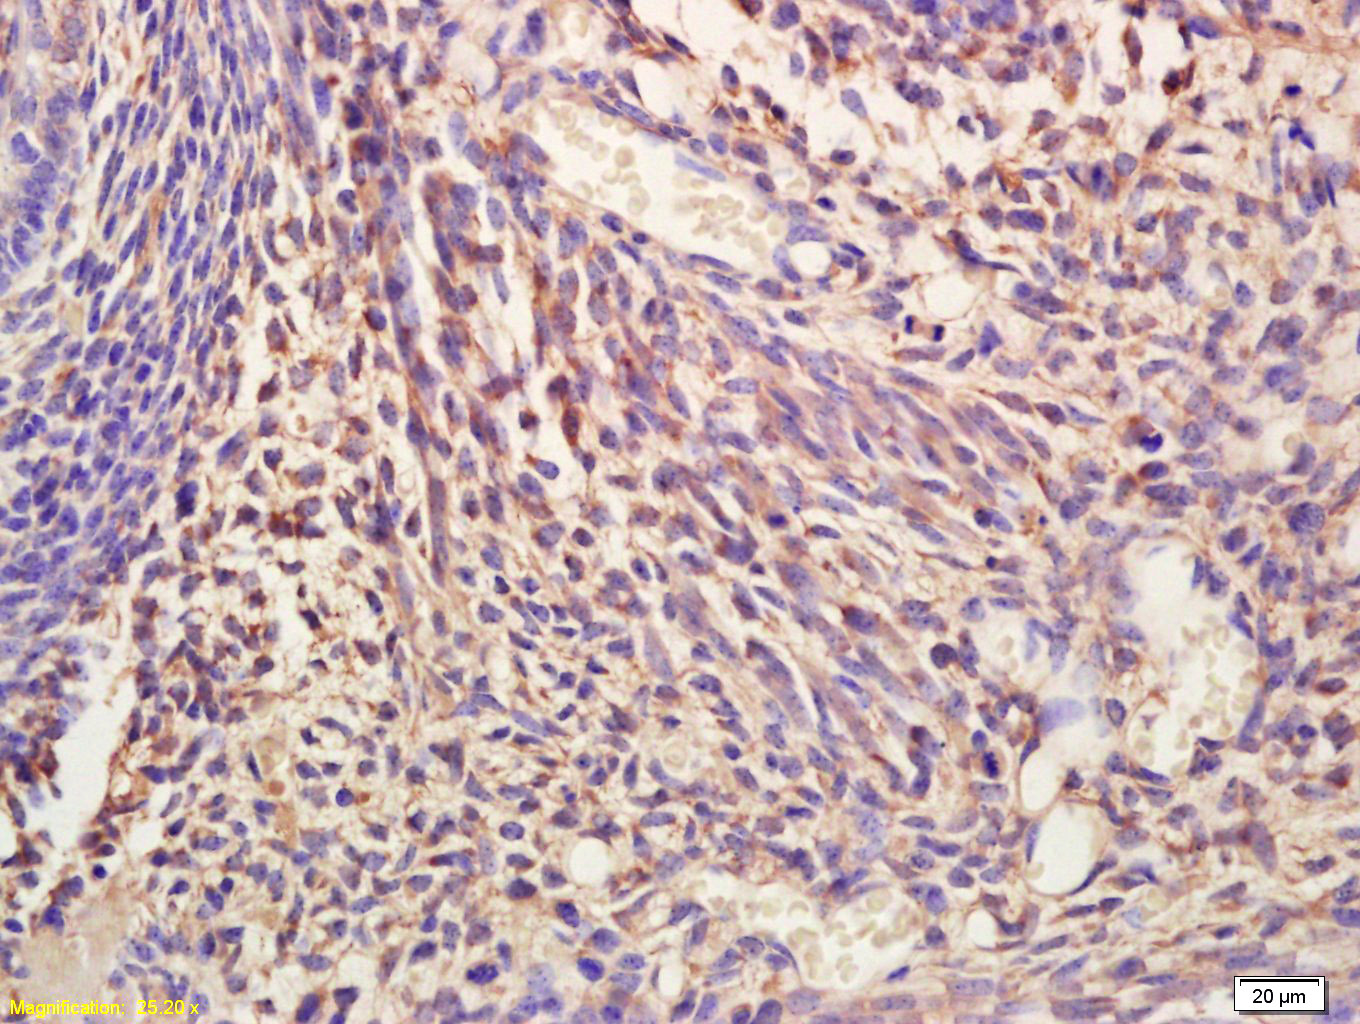

Paraformaldehyde-fixed, paraffin embedded (rat liver tissue); Antigen retrieval by boiling in sodium citrate buffer (pH6.0) for 15min; Block endogenous peroxidase by 3% hydrogen peroxide for 20 minutes; Blocking buffer (normal goat serum) at 37°C for 30min; Antibody incubation with (NIT2) Polyclonal Antibody, Unconjugated (bs-2012R) at 1:400 overnight at 4°C, followed by a conjugated secondary (sp-0023) for 20 minutes and DAB staining.

Tissue/cell: Mouse embryos; 4% Paraformaldehyde-fixed and paraffin-embedded; Antigen retrieval: citrate buffer ( 0.01M, pH 6.0 ), Boiling bathing for 15min; Block endogenous peroxidase by 3% Hydrogen peroxide for 30min; Blocking buffer (normal goat serum,C-0005) at 37℃ for 20 min; Incubation: Anti-BCAS3 Polyclonal Antibody, Unconjugated(bs-2012R) 1:200, overnight at 4°C, followed by conjugation to the secondary antibody(SP-0023) and DAB(C-0010) staining